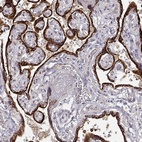

Immunohistochemical staining of human placenta shows strong cytoplasmic positivity in trophoblastic cells.